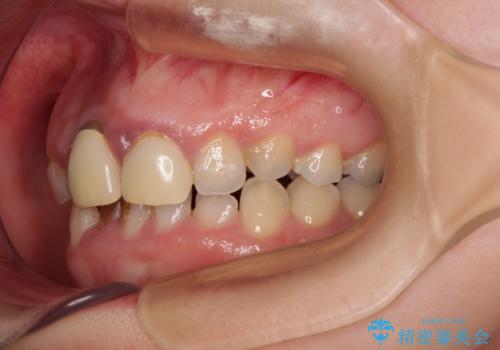

- 前歯のデコボコと、着色が著しい保険診療の前歯クラウンを気にして来院された患者様です。

左上の犬歯が埋伏しており、CT画像より萌出は困難と判断されたため、残存している歯にて歯列と咬合を整えることとしました。

マウスピース装着は煩わしいとのことで、表側のワイヤー装置にて矯正治療を行うこととしました。

前歯のクラウンは変色が顕著なため、矯正治療後にオールセラミッククラウンによる補綴治療を行うこととしました。